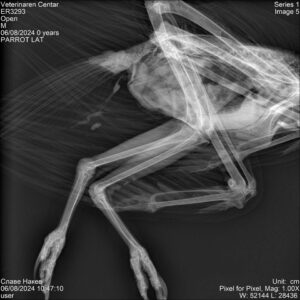

Наодите од обдукцијата на златниот орел кој угина во ЗОО Скопје August 22, 2024 Како и што ветивме. Штом ги добивме, веднаш ги објавуваме наодите